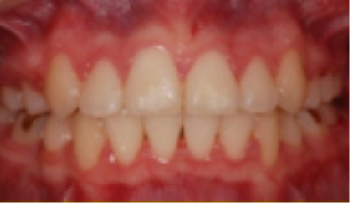

교정 치료 Before&After

• 상악 전돌(돌출) 위턱이 앞으로 나옴.

Before

After